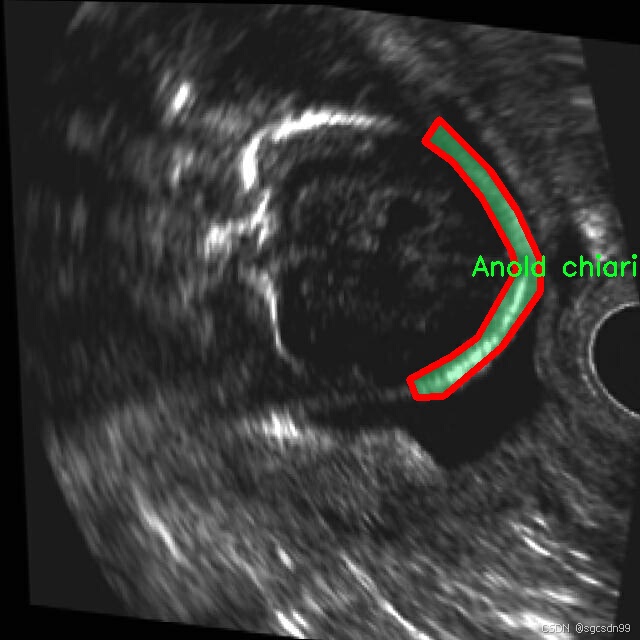

2.图片演示

names: [‘Anold chiari malformation’, ‘Arachnoid cyst’, ‘Cerebellah hypoplasia’, ‘Cisterna magna’, ‘Colphocephaly’, ‘Encephalocele’, ‘Holoprosencephaly’, ‘Hydracenphaly’, ‘Intracranial hemorrdge’, ‘Intracranial tumor’, ‘Mild ventriculomegaly’, ‘Moderate ventriculomegaly’, ‘Polencephaly’, ‘Severe ventriculomegaly’]

在现代医学影像学中,胎儿脑部异常的早期识别对于提高临床干预的有效性至关重要。为此,本研究利用名为“mask-rcnn-detectron2”的数据集,旨在训练一种改进的YOLOv8-seg图像分割系统,以实现对胎儿脑部异常的高效识别和分割。该数据集包含14个类别,涵盖了多种常见的胎儿脑部异常,具体类别包括:Anold chiari malformation(阿诺德-基亚里畸形)、Arachnoid cyst(蛛网膜囊肿)、Cerebellah hypoplasia(小脑发育不良)、Cisterna magna(大脑池)、Colphocephaly(脑室扩张)、Encephalocele(脑膨出)、Holoprosencephaly(全前脑发育不良)、Hydracenphaly(水脑)、Intracranial hemorrhage(颅内出血)、Intracranial tumor(颅内肿瘤)、Mild ventriculomegaly(轻度脑室扩大)、Moderate ventriculomegaly(中度脑室扩大)、Polencephaly(多脑半球发育)、Severe ventriculomegaly(重度脑室扩大)。

该数据集的丰富性和多样性为训练深度学习模型提供了坚实的基础。每个类别都代表了一种特定的胎儿脑部异常,这些异常在临床上具有重要的诊断意义。通过对这些类别的细致标注,研究人员能够训练出更为精准的模型,从而在实际应用中提高识别的准确性和效率。例如,阿诺德-基亚里畸形和全前脑发育不良是两种严重的脑部异常,及时的识别可以为后续的治疗方案提供重要依据。